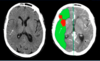

DX?

Infarto cerebral debido a ACM izq